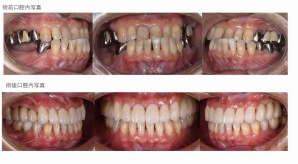

¥¤¥ó¥¹¥¿¥°¥é¥à¤ËºÜ¤»¤Æ¤¤¤ëÅö±¡¤Î¾ÉÎã¤Ç¤¹

ðÌî»õ²Ê¾ÉÎ㢠ÀèÅ··ç»¶ºÀµ¥¤¥ó¥×¥é¥ó¥È